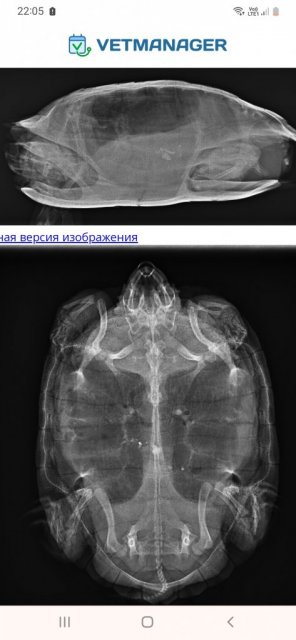

Здравствуйте, прошел почти месяц с начала лечения черепашки. До Ярослава мы не доехали, он согласился на консультацию по телефону, скинули ему назначение врача, рентген, фото черепахи и домика. Он одобрил лечение и все назначения Анны Павловны, даже температуру воды. Антибиотик проколали, увеличили ингаляции еще на неделю, чтоб с антибиотиком вместе подействовало. Сегодня ездили на повторный  рентген, сказали "динамика положительная". Не знаю,  означает ли это выздоровление, но повторно попросили приехать через год на рентген и кровь.  Осталось разобраться с водой в аквариуме, но я создала отдельную тему под это. Пушистик еще не линял, надеюсь,  с переходом на рептомин начнёт ?

Screenshot_20240118-220532_Chrome.jpg

Screenshot_20240118-220522_Chrome.jpg

а ничего не говорили про что-то рентгеноконтрасное на снимках в теле? у неё никогда грунта не было?

@moth Первый рентген был такой.  Думаем, пообдирала камушки со старого аквариума. Сейчас грызла искусственную траву, но понемногу интерес к ней угасает. На этот раз ничего про рентгеноконтрастное не говорили, надеюсь,  тоже выйдет естественным путем. Понаблюдаем за ней.

@moth Спасибо,  просто после пневмонии она мне теперь всегда мерещится. Буквально не даёт покоя одна мысль. На рентгене легкие мутные, не чёрные(как везде показывают). Врач сказала, что черными они не будут из-за органов и карапакса. Почему у некоторых они прям чисто черные на рентгене? Это тоже вариант нормы?